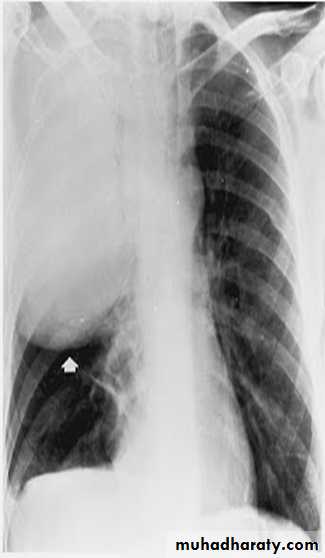

Legionnaires' disease ; No diagnostic features on the chest X-ray distinguish it from other pneumonia. But may showing pulmonary infiltrates ;Infiltrates can be unilateral, bilateral, patchy, or dense, and In sever illness it m. be multilobar involvement ,can spread very quickly to involve the entire lung.

Chest X-ray show multiple lung abscessStaphylococcus pneumonia

In lobar pneumonia, a homogeneous opacity localized to the affected lobe or segment usually appears within 12-18 hours from the onset of the illness.If a complication such as parapneumonic effusion, intrapulmonary abscess formation, or empyema is suspected.

Clinical-radiographic dissociation is seen often in patients with Mycoplasma pneumoniae or viral pneumonia.

Lateral radiographs are especially important in showing infiltrates, which may be obscured by the heart on posteroanterior projections.